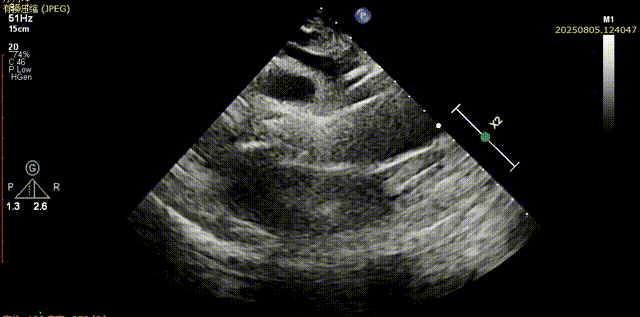

输送器顺利跨瓣,部分释放后,可见喇叭口结构,开始定位释放,180次/分起搏下展开至工作位,超声评估可见位置可,二尖瓣活动良好,瓣周反流较少,综合考虑瓣膜锚定良好,脱钩释放

输送器跨瓣

瓣膜展开至工作位

工作位评估1

工作位评估2